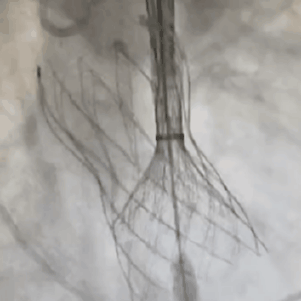

从三叶瓣重度钙化到二叶瓣畸形的根部解剖,从单纯主动脉瓣反流到入路极端迂曲挑战的案例。TaurusOne凭借其优异的柔顺性,支撑力强及内外层双侧裙边的特点,都能从容应对复杂的临床患者解剖结构。从患者的临床选择到术后的长久获益,从手术入路的种类到术中操作的注意事项,从围术期卒中的循证医学到术后的抗凝抗栓用药规范,在线专家共同交流彼此中心的围术期TAVR经验和分享现阶段经导管主动脉瓣置换的诊疗策略。针对当前TAVR领域多个热点学术问题进行了热烈的讨论,现场可谓精彩纷呈、高潮迭起。专家们纷纷借此契机相互交流探讨,分享各自的单中心经验,力求进一步提升TAVR手术的安全性和有效性,为主动脉瓣相关疾病的患者带来长远综合获益。